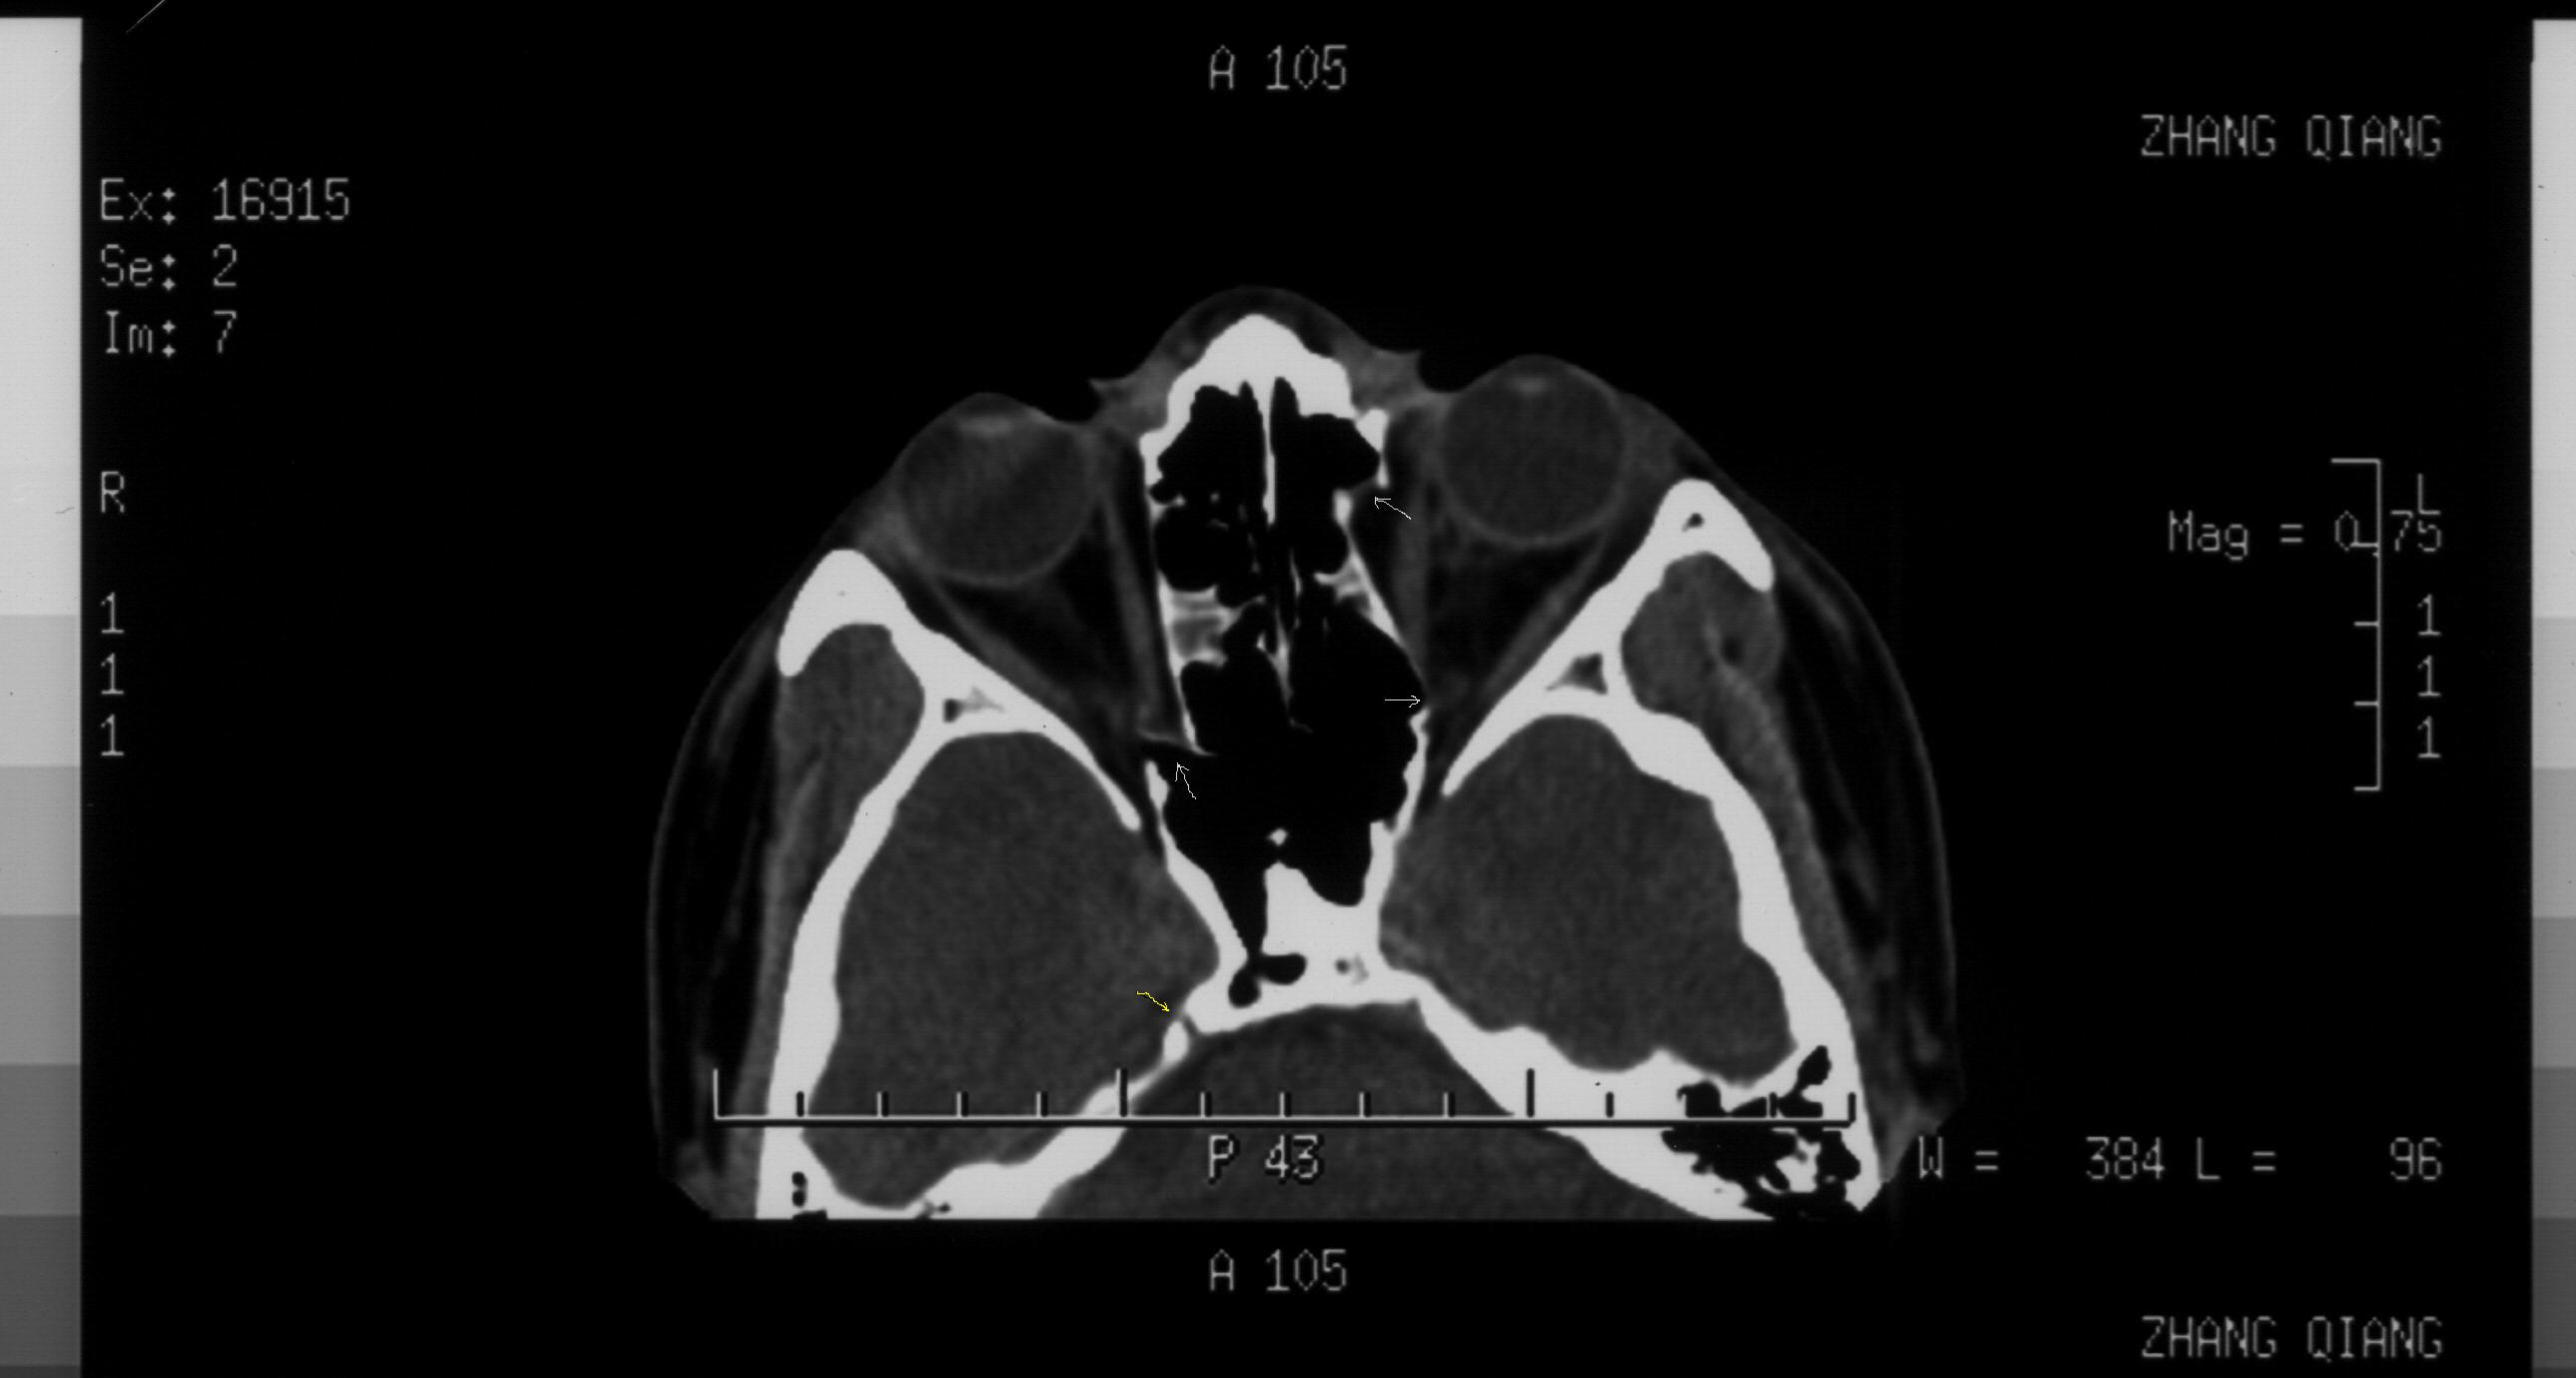

双眼拳击伤 双眼全方位复视 请解读一下ct片 如何治疗 谢谢

你好! 关于你的CT片的质量问题,也许不能、马上解决,不过请以后再选片时,注意以下三个问题:1、外伤患者应有至少一张包括视神经层面。2、尽量标明TOPO定位像3、请对关键层面给出软组织窗。就目前情况,我们确实有猜 的成分。好了,言归正传。

你的CT片分析结果,至少有两点是可以确定的。1、双侧眼眶内侧鼻多发骨折 2、鼻骨骨折。 |

本人高度怀疑有内直肌近腱环处撕裂伤抑或是合并嵌顿。如同所述,则是急诊手术的绝对适应症,不能延误。 手术如何做?? |